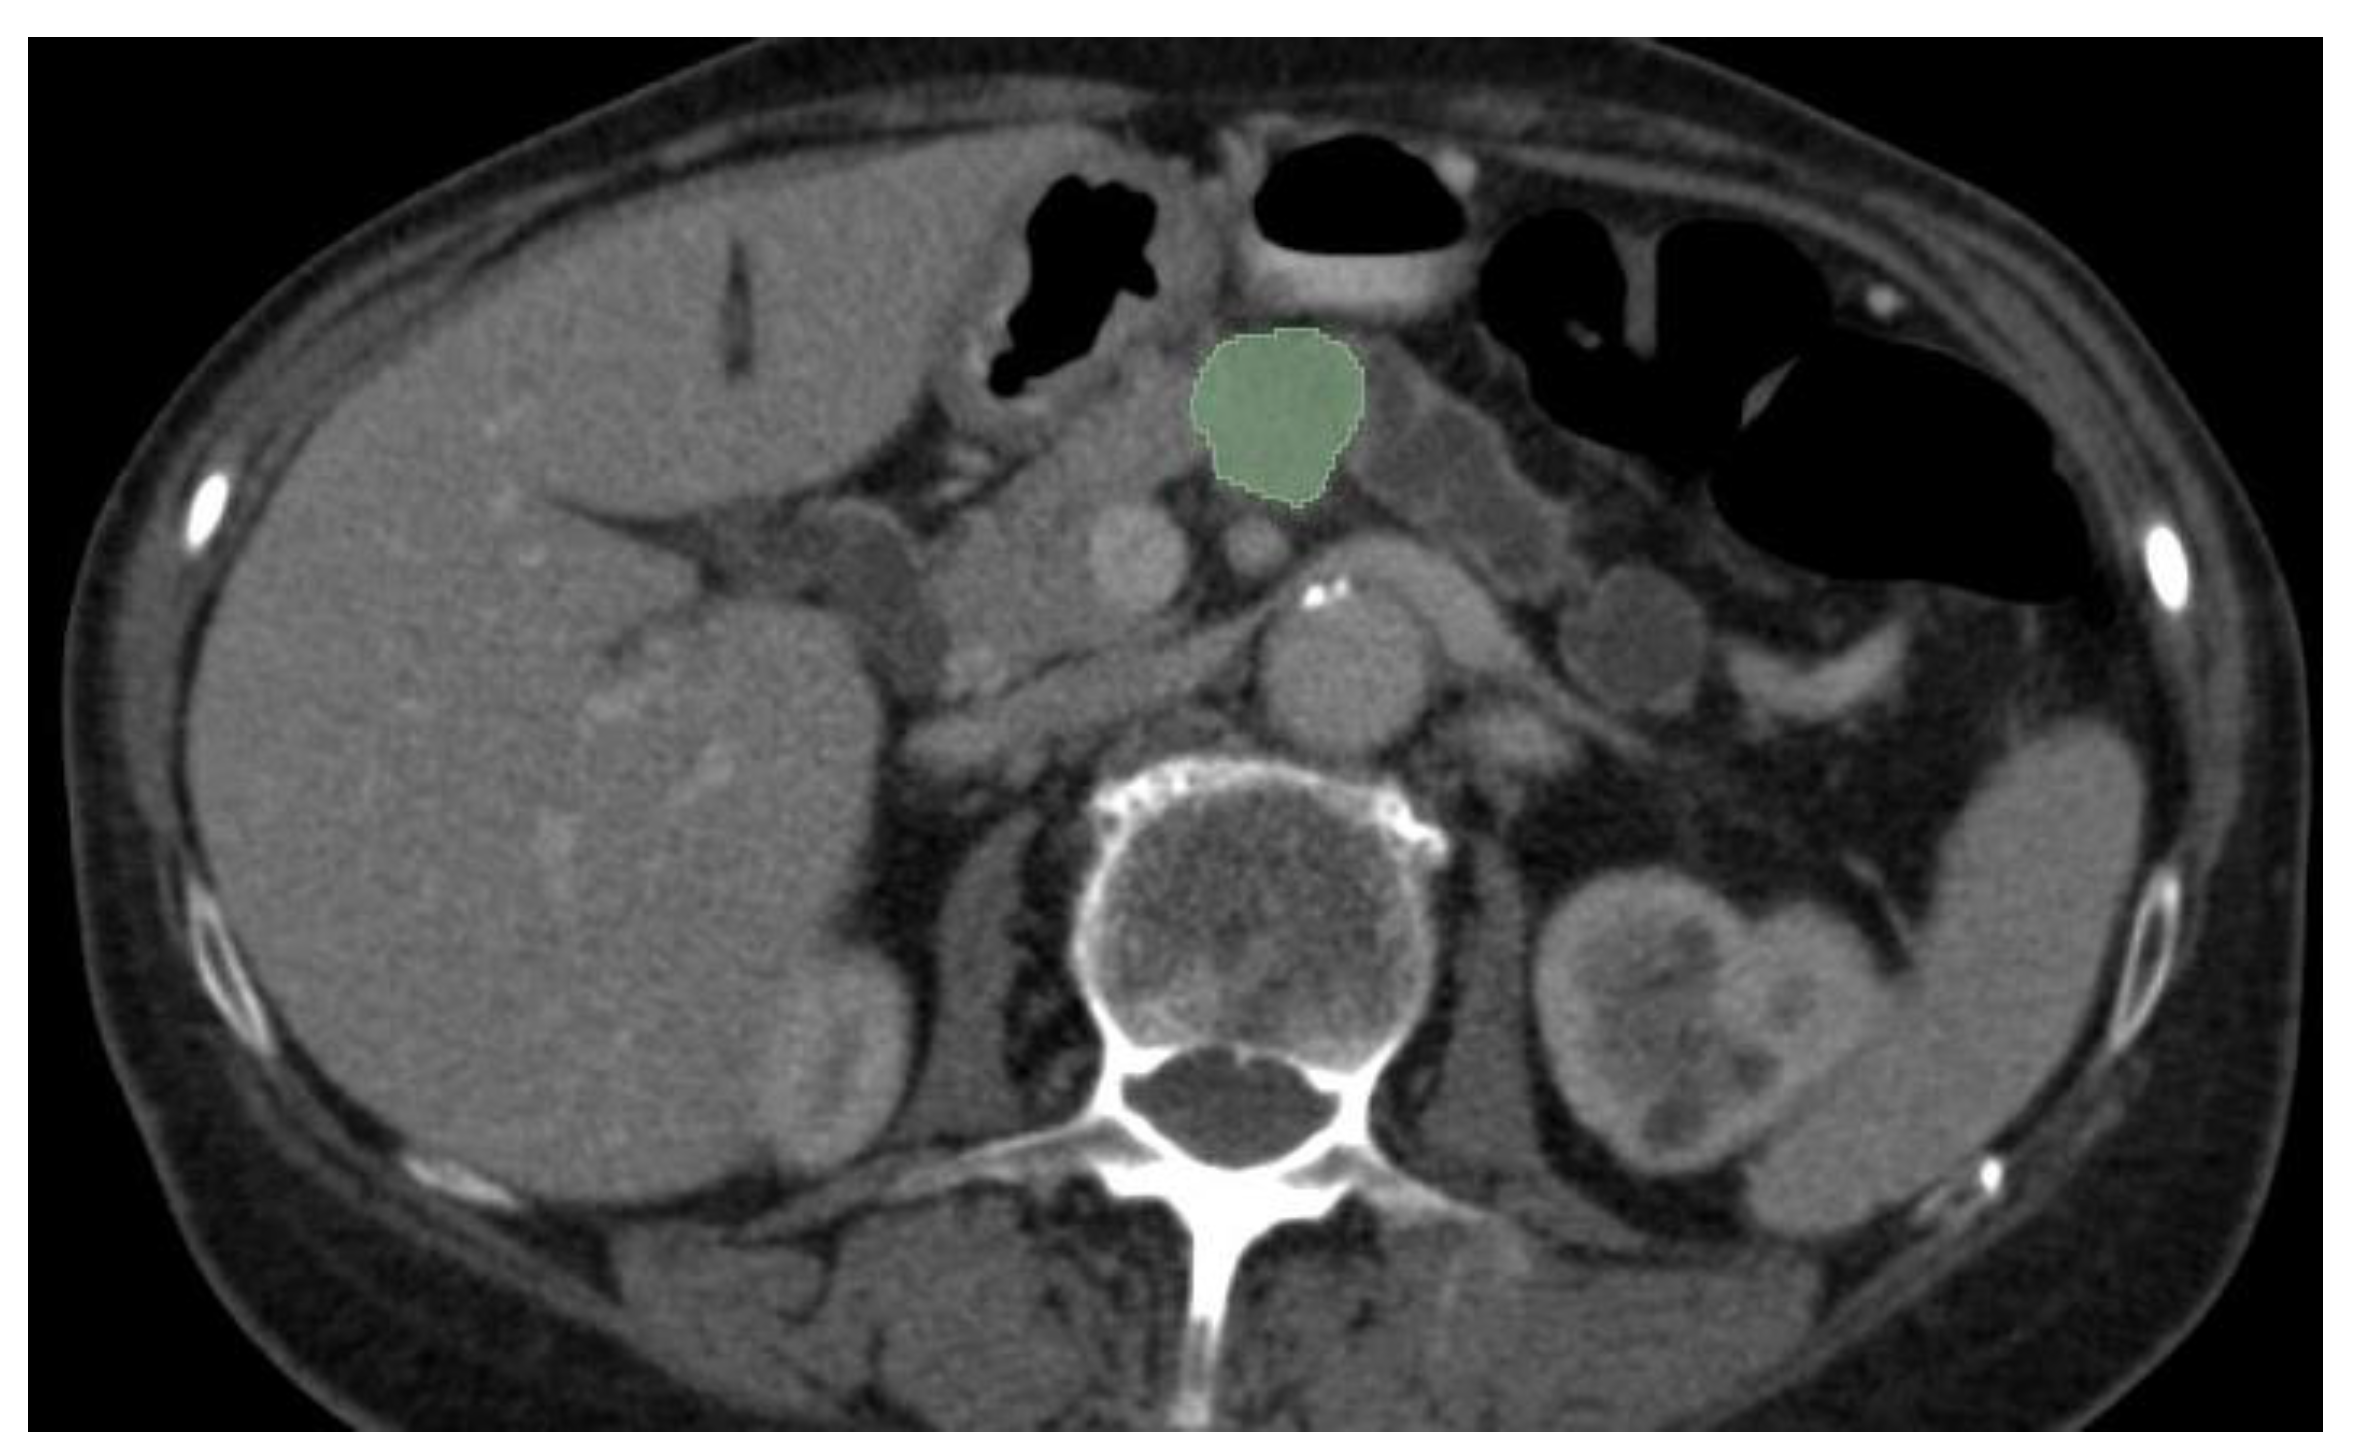

Most of the AI radiology models are supervised and need large amounts of images for training[50]. Image preparation including lesion and organ segmentation is done in most instances manually or in a semi-automated manner by the radiologist. This process needs huge amount of work and given the fact that for AI models to be validated large datasets are needed for training and testing, a great interest in automatic segmentation of the pancreas and pancreatic lesions is seen in the last years. An example of semi-automated tumor segmentation using 3D Slicer software (https://www.slicer.org/) is shown in Figure 4.

Figure 4. CECT portal venous-phase showing semi-automated corporeal pancreatic tumor segmentation (depicted in green) using “growing-seeds” method.